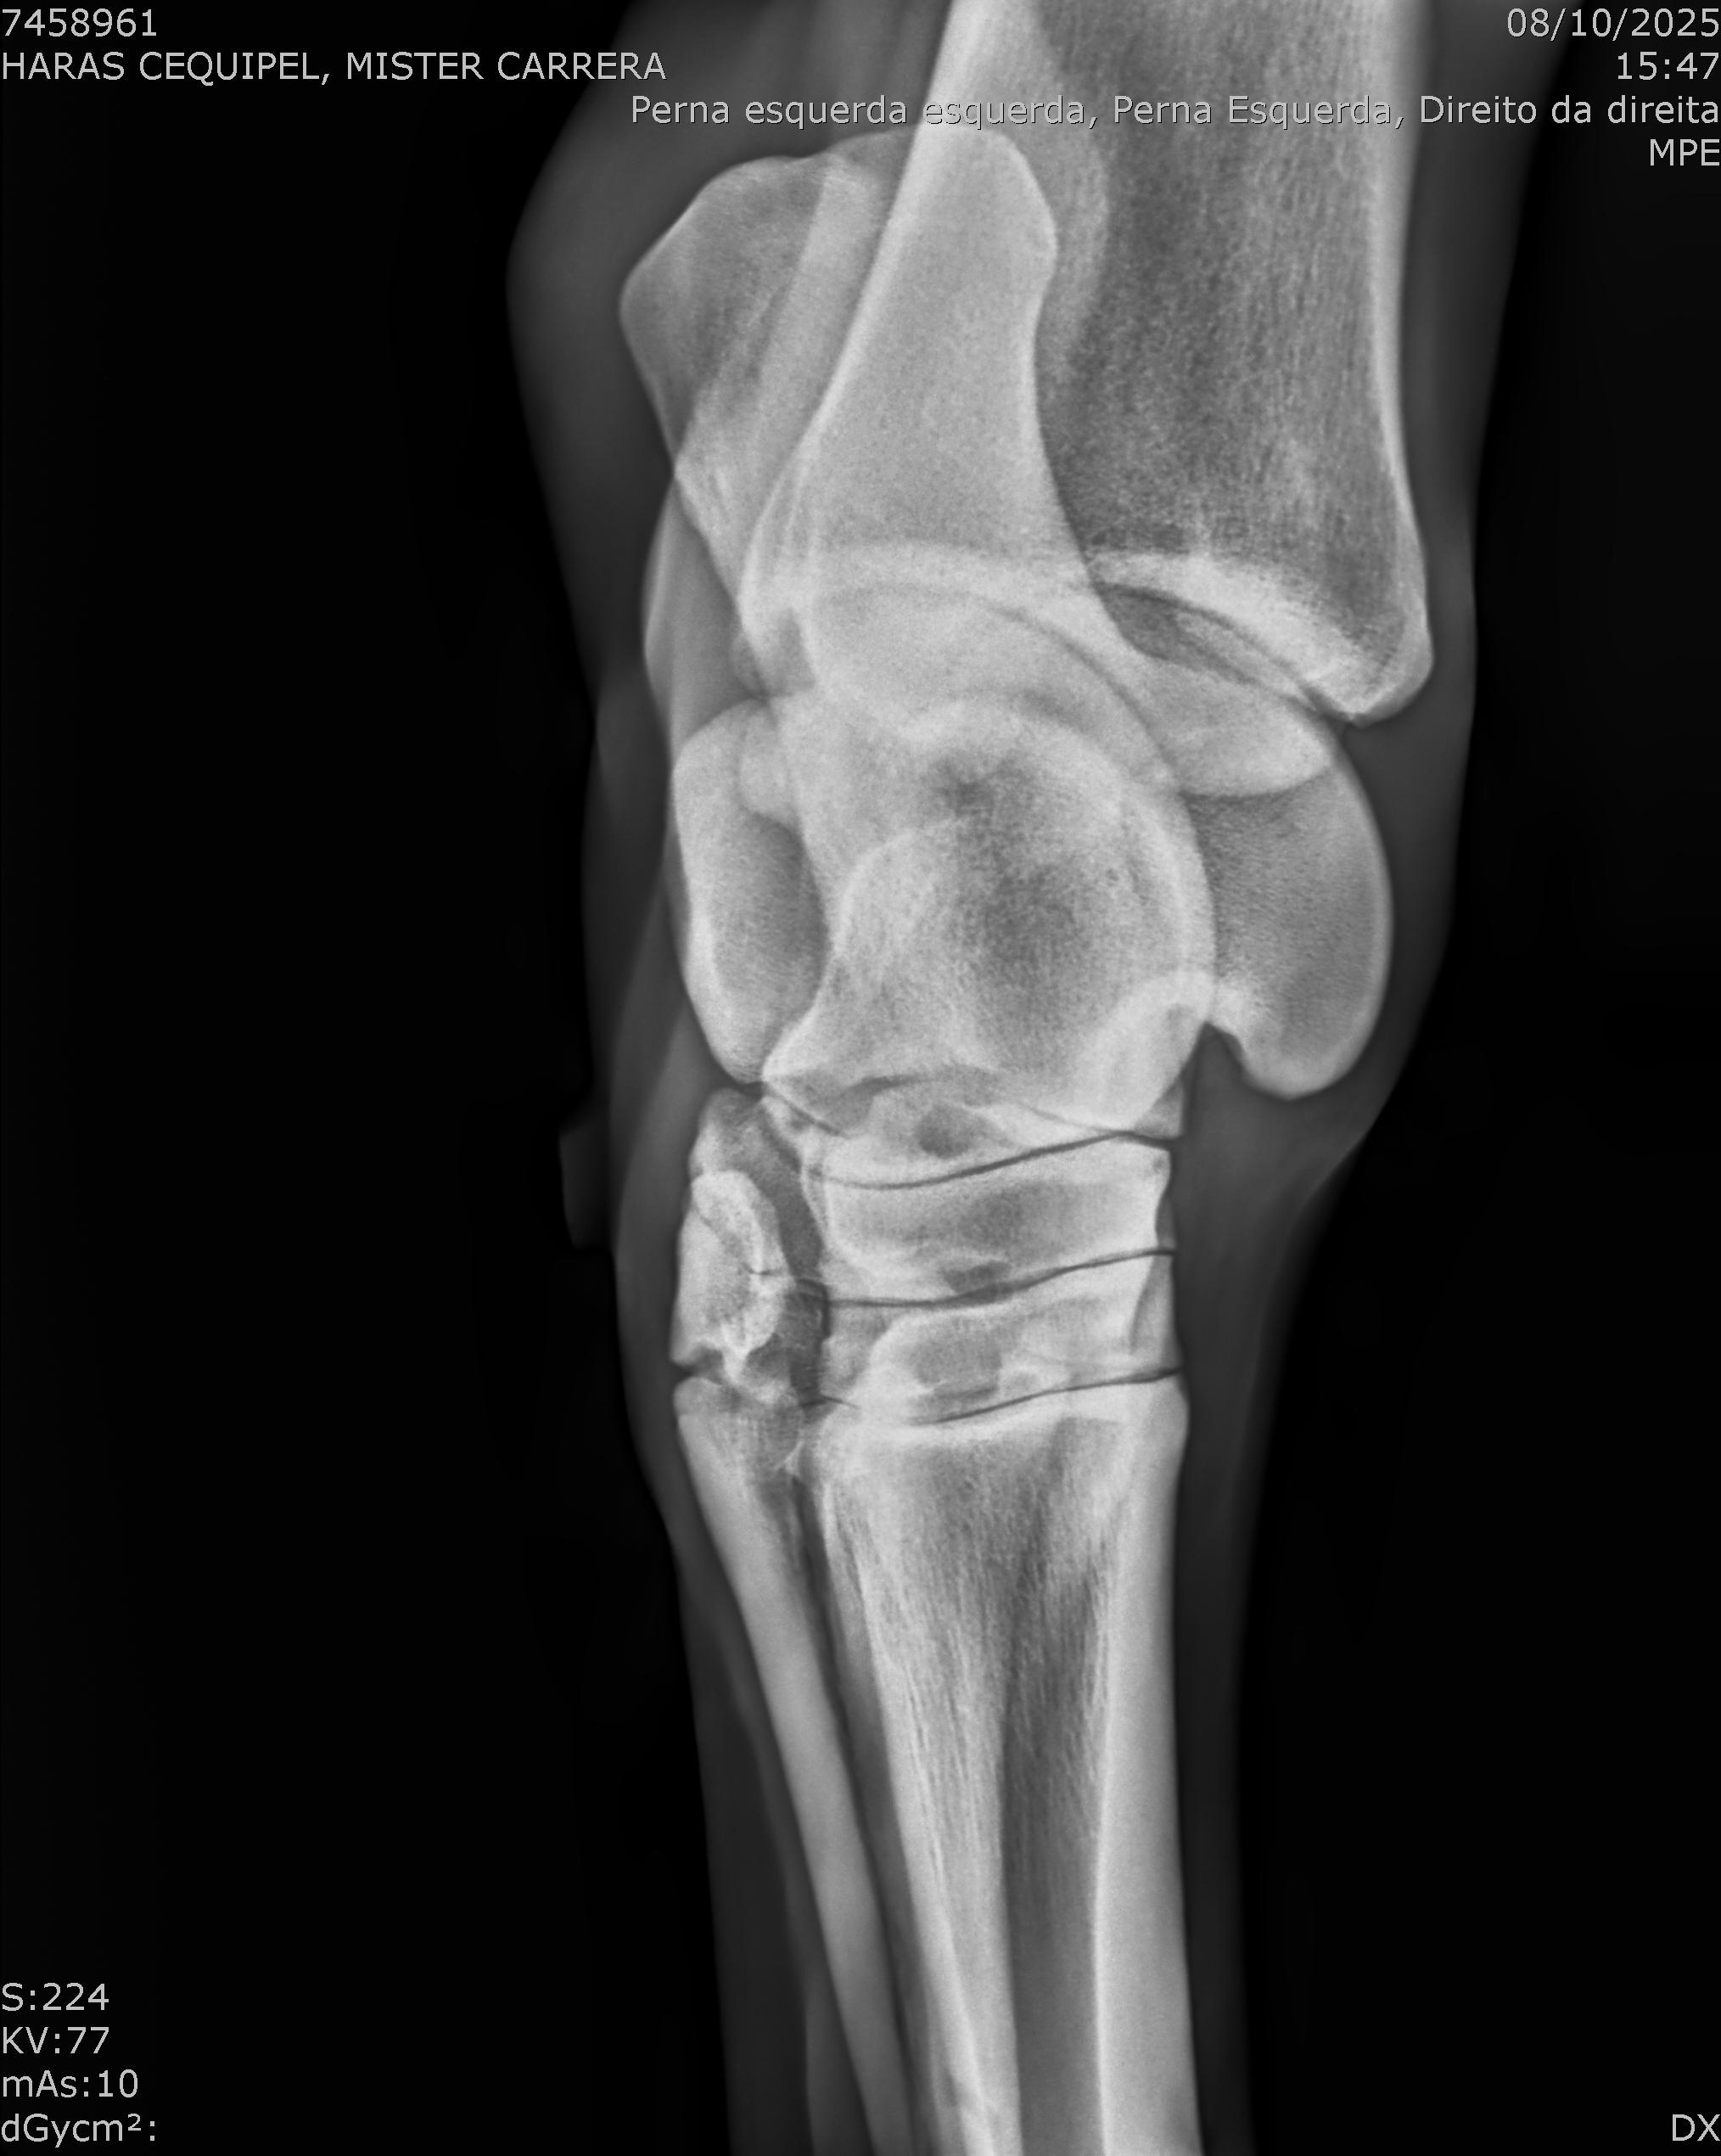

:: RAIOS-X DO LOTE